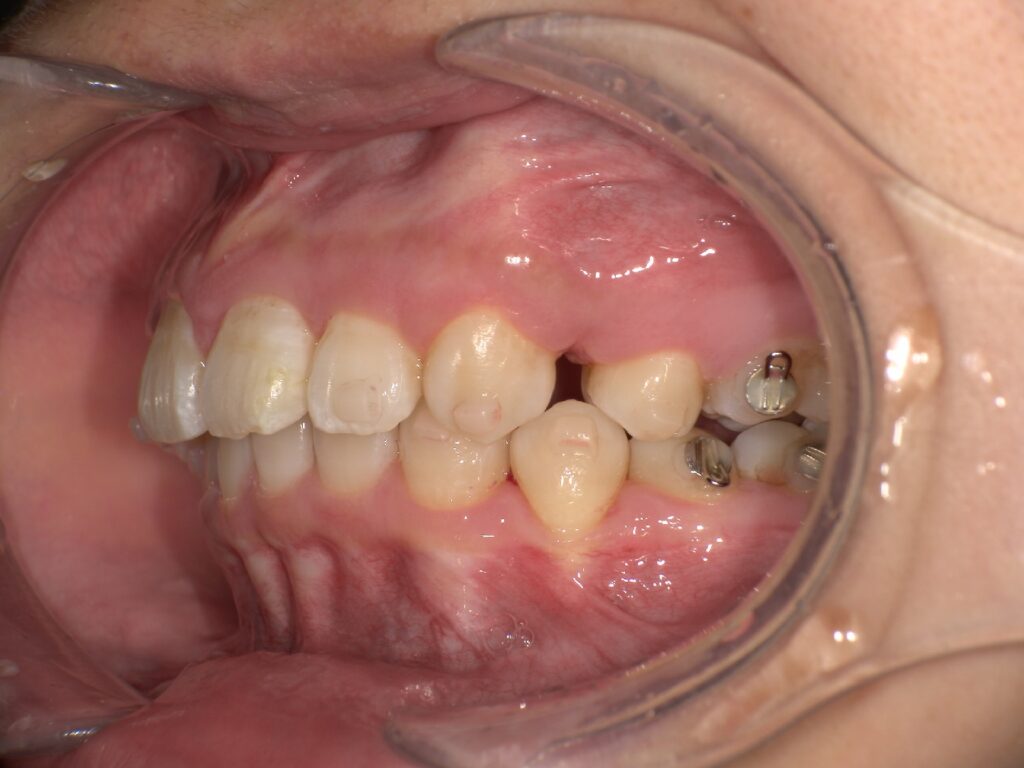

下記のケースでは、奥歯の噛み合わせが悪くなかったことから、患者様の希望もあり、部分矯正で対応いたしました。

上顎の前歯が大きく突出しています

明らかに前歯の突出感が改善し、患者様はこの時点でとても喜ばれていました

矯正治療終了時 部分矯正ということもあり、短期間で矯正治療を終了することができました